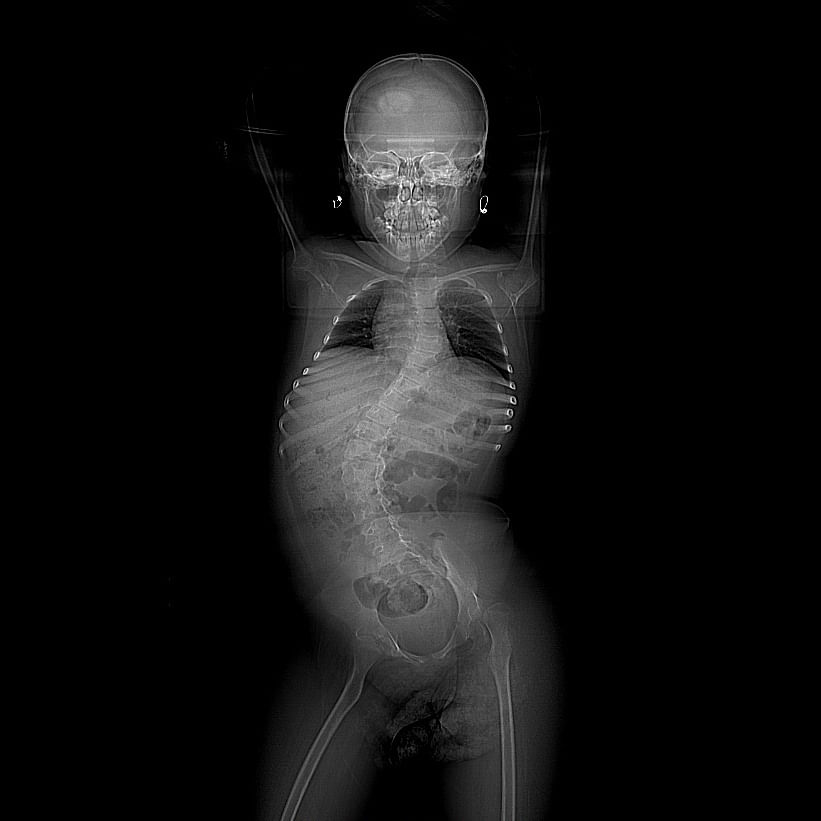

Ich zeigte Andreeas Röntgenbilder dem auf Wirbelsäulen-Operationen spezialisierten Kinder-Orthopäden Alexandru Thiery und fragte ihn, was in ihrem Fall die geeignete Therapie wäre. „Ich hätte gewartet, bis Andreea zehn Jahre alt ist. Dann wäre bei ihr eine herkömmliche Wirbelsäulenversteifung möglich gewesen”, sagt Thiery. Zur Verringerung der Skoliose des Mädchens hätte es noch andere Möglichkeiten gegeben: „Dual Growing Rod” ist derzeit eine Standard-Technik.